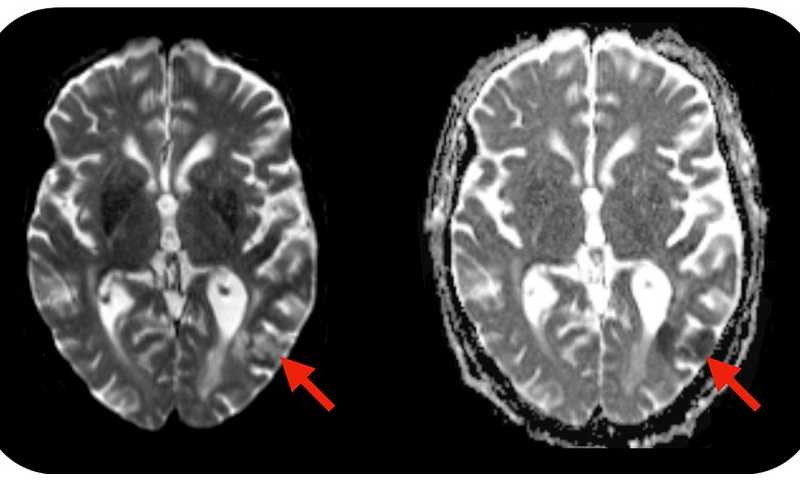

CAR-T-клеточная терапия, с одной стороны, спасает жизни пациентов с некоторыми плохо излечимыми типами рака, с другой, вызывает тяжелые осложнения. В их числе такие опасные побочные эффекты, как синдром высвобождения цитокинов и синдром нейротоксичности, ассоциированной с иммунными эффекторными клетками (immune effector cell–associated neurotoxicity syndrome, ICANS). Развивается ICANS у 40–60% пациентов, проходящих CAR-T-клеточную терапию, при этом первые симптомы проявляются уже на 3–9 день после введения препарата. Иногда все заканчивается серьезными поражениями головного мозга — энцефалопатией, отеком мозга, а также летальным исходов. Очевидно, что избежать подобных осложнений помогло бы выявление риска развития ICANS у пациентов на ранних этапах иммунотерапии, а лучше — до ее начала.

Команда ученых в основном из Вашингтонского университета в Сент-Луисе проанализировала образцы крови 30 пациентов, страдающих В-клеточной лимфомой, до начала CAR-T-клеточную терапии, во время лимодеплеции (удаления собственных клеток, способных снижать активность CAR-T-лимфоцитов) и в течение 30 дней после введения препарата. У пациентов, у которых развился ICANS, обнаружен высокий уровень белка NfL (от англ. Neurofilament Light chain — легкая цепь нейрофиламента), причем не только во время и после лечения, но и до его начала. Авторы предполагают, что это связано с латентными нарушениями функциональности нейронов.